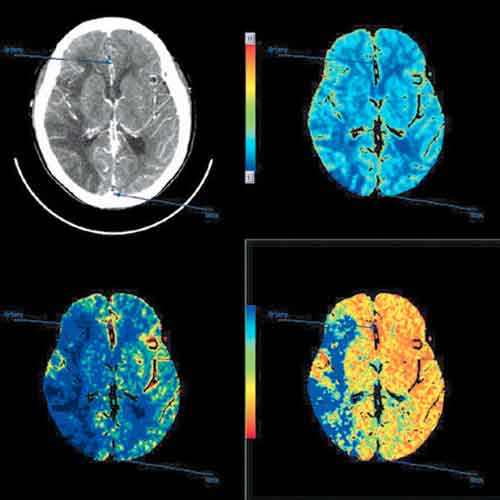

Gli esami di imaging sono stati identificati come uno dei fattori chiave dell’aumento dei costi sanitari. Un nuovo studio del Brigham and Women ‘s Hospital e della Harvard Medical School ha individuato delle significative variazioni nell’utilizzo della tomografia computerizzata (CT) anche all’interno di uno stesso dipartimento di emergenza, mettendo cosi’ in evidenza che potrebbero essere adottate delle strategie per ridurre tali anomalie nell’uso della CT in modo da ridurre i costi sanitari e migliorare la qualita’ delle cure.